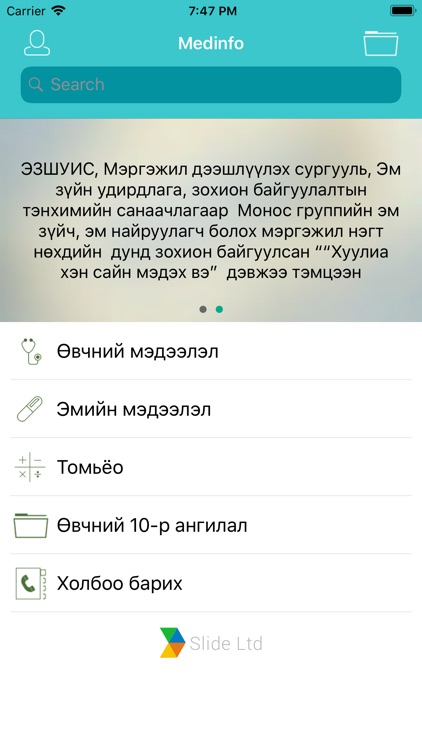

Эрүүл мэндийн лавлах аппликейшн

Medinfo - Эрүүл мэнд

Эрүүл мэндийн лавлах аппликейшн.

Эрүүл мэндийн лавлах аппликейшн.